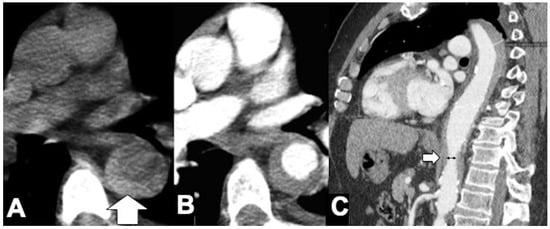

| Hyperattenuating crescent sign | - | + | |

| Draped Aorta sign | - | + | |

| Missing calcium sign | - | + | |

| Tangential calcium sign | - | + | |